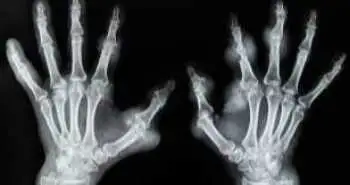

Недавнє контрольоване, рандомізоване та відкрите дослідження, що його опублікували в «Scientific reports», показало, що використання комбінованої з біосиміляром етанерсепта (рекомбінантного рецептору другого типу до фактору некрозу пухлини альфа, із змішаним імуноглобуліном lgG Fc (rhTNFR-α: Fc fusion protein injection (Fc)), терапії метотрексатом (MTX) при активному перебігу РА, досить ефективно проти діяло ураженню хрящової суглобової тканини.

Дослідники оцінили ефективність та безпеку використання комбінації MTX з підтримуючою терапією rhTNFR:Fc, чи її зупинкою,  у пацієнтів з активним перебігом РА. Включили 89 відповідних пацієнтів. Через 52 тижні, пацієнтів розділили на 2 групи, що отримували: MTX із rhTNFR:Fc на протязі 52 тижнів (32 пацієнти), або MTX з rhTNFR:Fc на протязі 24 тижнів (31 пацієнт), чи тільки MTX (26 пацієнтів).

Ураження хряща оцінювали модифікованим показником ван дер Хейда (van de Heijde modified Total Sharp Score (mTSS)), що було первинною кінцевою точкою (ПКТ). З групи отримуючих  MTX з rhTNFR:Fc 24 тижні, на протязі періоду спостереження вибув один пацієнт. Оцінюваний показник mTSS CFB був нижчим у об’єднаній групі тих, що отримували rhTNFR:Fc, порівняно з монотерапією метотрексатом, як на 24-й,  так і на 52 тиждень, за досліджені проміжки часу (Графік 1).

Графік 1:  ПКТ (mTSS CFB) на 24 та на 52 тиждень у трьох групах.

Більше того, підвищені оціночні рівні відповіді згідно з критеріями ACR50 та ACR70, спостерігали у об’єднаній групі тих, що отримували rhTNFR:Fc, порівняно з монотерапією метотрексатом.

Дане дослідження проливає світло на факт, що у пацієнтів з активним РА, пригнічення ураження суглобового хряща може бути досяжним за умови використання комбінації MTX та rhTNFR:Fc. Більше того, дана комбінація добре переноситься.